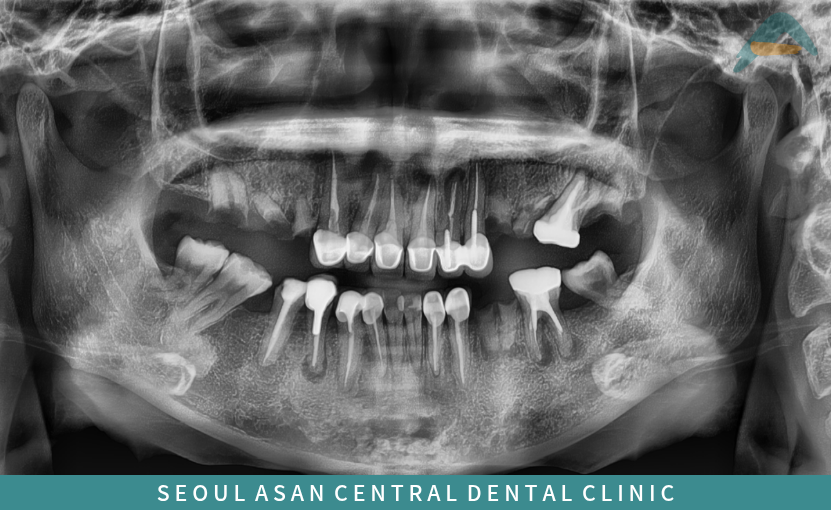

다수의 치아가 상실되어 있고

치관이 파절되어 치근만 남아 있는 경우에는

잔존 치아들의 지지력이 전반적으로 약화되어

동요도가 증가한 상태로 관찰되는 일이 많습니다.

이와 함께 치주 지지조직의 손상이 동반된 치아들은

장기적인 예후가 좋지 않은 경우가 적지 않으며,

보존 가능 여부에 대한 면밀한 평가가 필요합니다.

또한 양측 구치부가 상실된 상태가 지속되면

저작 시 하중을 분산시키는 기능이 떨어지면서

교합 균형이 무너지기 쉽습니다.

이로 인해 치아 배열의 불균형이 심화되고,

결과적으로 교합 고경이 감소된 소견이 나타나기도 합니다.

파노라마 상에서도

치아들이 빈자리로 쓰러져 있는 모습이 확인되며,

뿌리 끝 주변으로 염증이 형성된 치아들도

다수 관찰되는 경우가 있습니다.